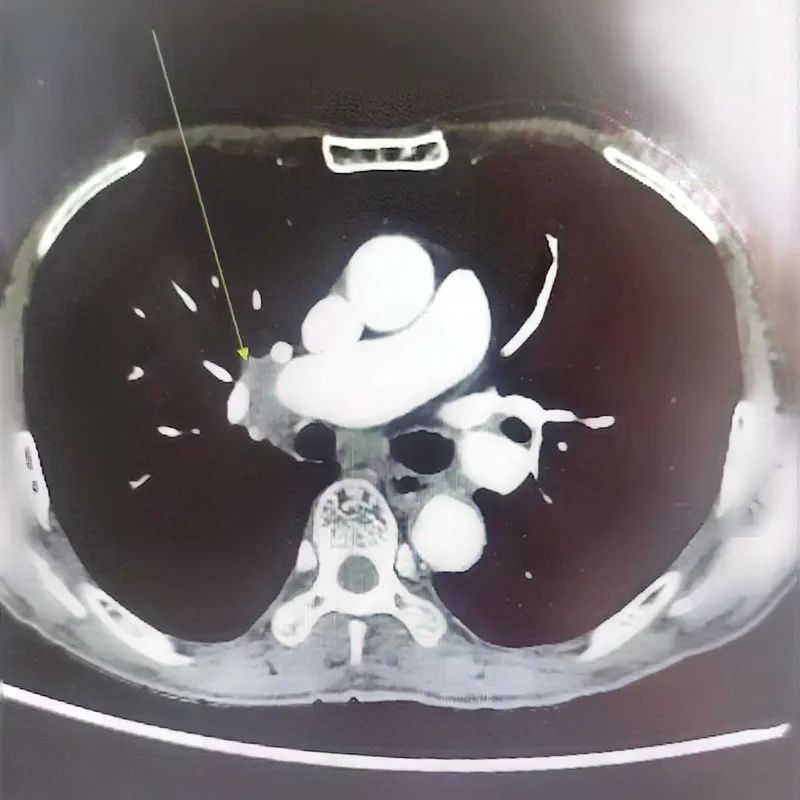

▲新辅助治疗前CT

患者66岁,男性,重度吸烟,在我院住院治疗,首次诊断为右肺腺癌T3N2M0 IIIB期,驱动基因野生型。患者为局部晚期肺腺癌,为此组织了第一次肺癌MDT,考虑患者肿瘤大,与血管关系密切,纵隔淋巴结肿大,肿瘤完全包绕右上肺、中肺动脉,手术难度极大、未能实现完全切除(R0切除),复发率高,故MDT专家意见:根据最新国际研究进展,先行新辅助治疗后再行评估。为此,患者接受了3疗程的免疫治疗+化疗,复查CT示肿瘤显著缩小,达到部分缓解(PR)。家属欣喜地说“本来对化疗非常抗拒,担心老父亲会承受不了,但出于对医疗组的信任,坚持给父亲选择最好的方案。才发现目前的化疗不会像老百姓想象中的恐怖,就是打3-4个小时的针水,做好定期抽血,老父亲也没有出现严重副作用,能吃能睡。看到肿瘤缩小很欣慰。”